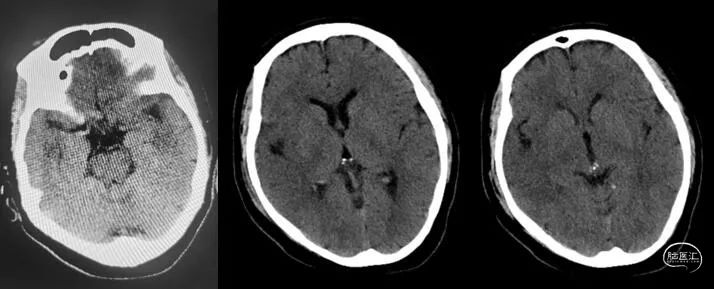

术前多模CT:右侧颈内动脉无嫌疑;CT平扫:大脑中动脉高密度帧,颞叶、岛叶脑沟、脑回灰质、白质分界不清;多模CT评估:缺血半暗带约198ml。

23:25:复查CT:

加重前后CT平扫比较(左加重前,右加重后):